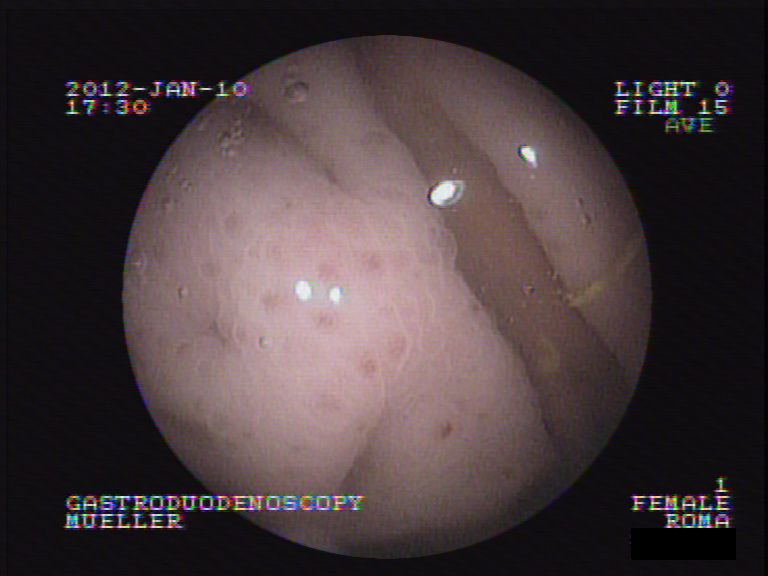

Nun wird als letzter Schritt das Problemorgan Magen direkt inspiziert. Unter Narkose wird eine Magenspiegelung durchgeführt - über die digitale Optik kann so die Magen- und Darmschleimhaut begutachtet werden.

Bei Roma zeigt sich, dass die Magenschleimhaut über weite Strecken glasig-weisslich erscheint. Sie enthält aber keine Blutungen, auch scheint der Magenausgang normal durchgängig und die Darmschleimhaut des oberen Dünndarms scheint normal. Durch einen Arbeitskanal im Endoskop werden mittels einer Biopsiezange mehrere Gewebeproben der Schleimhaut entnommen und in einem externen Labor untersucht.